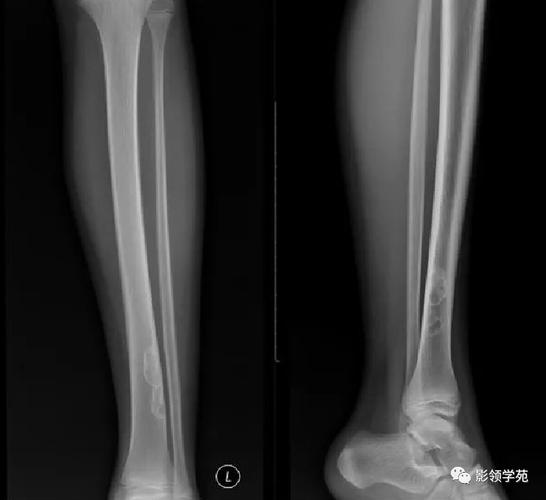

X光片(首选检查)

这是诊断该病的金标准,典型的X光片表现是:

- 位置:长骨的干骺端,靠近骨骺线。

- 形态:圆形或椭圆形的、边界清晰的透亮区(“空洞”)。

- 大小:通常较小,直径一般小于2厘米。

- 特征性表现:病灶的长轴与长骨的骨干平行,这是与其他骨病变(如骨样骨瘤、尤文氏肉瘤等)相鉴别的一个重要特征。